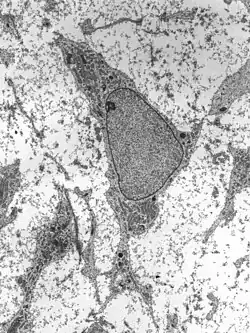

As células-tronco ou células estaminais são células que permanecem indiferenciadas, ou seja, ainda não passaram pelo processo de diferenciação celular. Podemos definir célula estaminal como uma célula que, quando se divide, produz uma célula que retém esse caráter indiferenciado e uma segunda célula que pode sofrer diferenciação.[1] Com isso, vemos que uma célula estaminal tem o potencial de se renovar a cada divisão, enquanto também produz uma célula nova capaz de responder ao seu ambiente, diferenciando-se de maneira particular (esse potencial nem sempre se verifica: algumas células-tronco dividem-se simetricamente, de modo que ambas as suas novas permanecem células estaminais).[1] Algumas células-tronco adultas são capazes de se diferenciar em mais de um tipo celular, como as células-tronco mesenquimais e as células-tronco hematopoiéticas, enquanto outras são consideradas precursoras diretas das células do tecido em que são encontradas, como as células-tronco da pele ou as células-tronco gonadais.

Uma célula estaminal tem uma extensa capacidade de proliferação, criando mais células estaminais (utilizada para manutenção de um devido organismo, pois garante uma autorrenovação constante, como, por exemplo, as células sanguíneas) e criando descendentes celulares diferentes.[2] As células estaminais são um conjunto embrionário de células que se mantêm mesmo em organismos adultos.[2] Células-tronco embrionárias são aquelas encontradas no embrião com até 4 a 5 dias de idade e têm a capacidade de formar todos os tipos celulares de um organismo adulto. Uma característica fundamental das células-tronco embrionárias é que elas podem ser mantidas (no corpo ou numa placa de cultivo) indefinidamente. O fato de uma única célula-tronco ser capaz de formar quase qualquer tipo de célula abre espaço para o uso dessas células como forma de experimentação para curar doenças ou regenerar tecidos danificados, como ocorre no ramo da ciência chamado engenharia de tecidos.